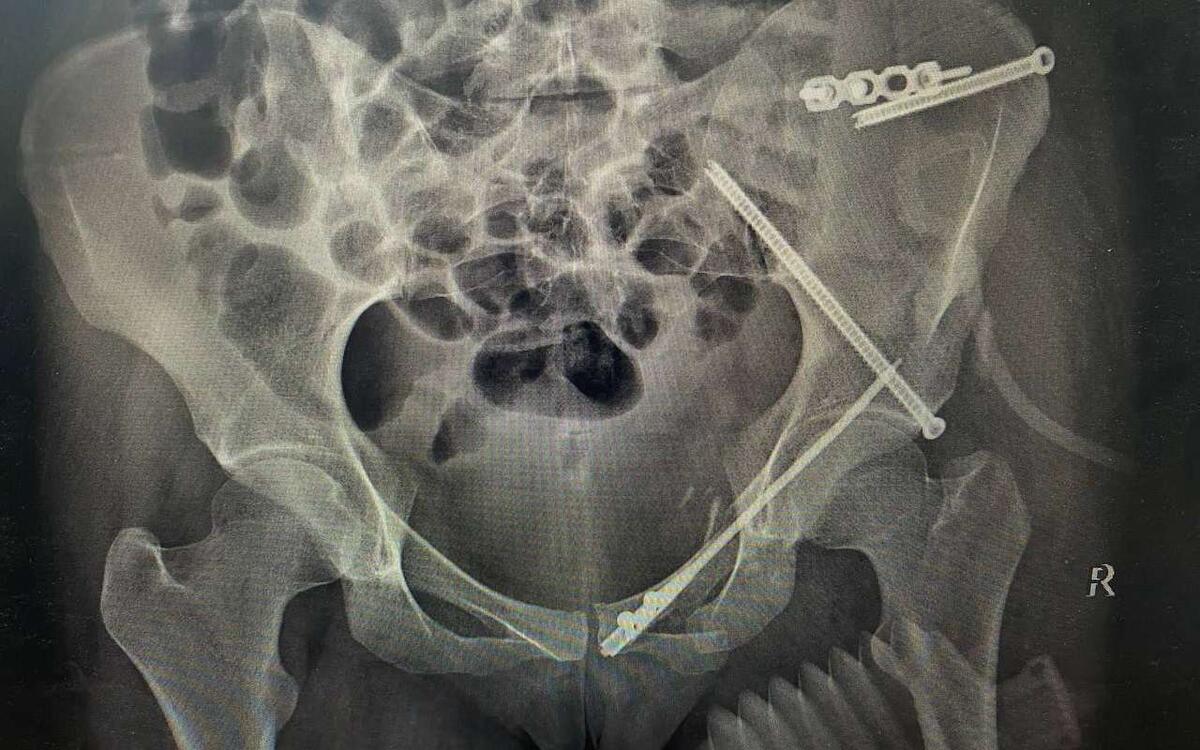

Девушке провели обследование и предоперационное планирование с использованием 3D-моделей. После этого бригада врачей провела операцию по металлоостеосинтезу, когда кости таза фиксируют при помощи винтов и титановых пластин.

Операция прошла успешно. Врачам удалось снизить кровопотерю, уменьшить болевой синдром и надежно зафиксировать кости таза. Во время операции пациентке сделали небольшие надрезы. Это способствует более быстрому сращиванию переломов, а шрамы останутся почти незаметными.